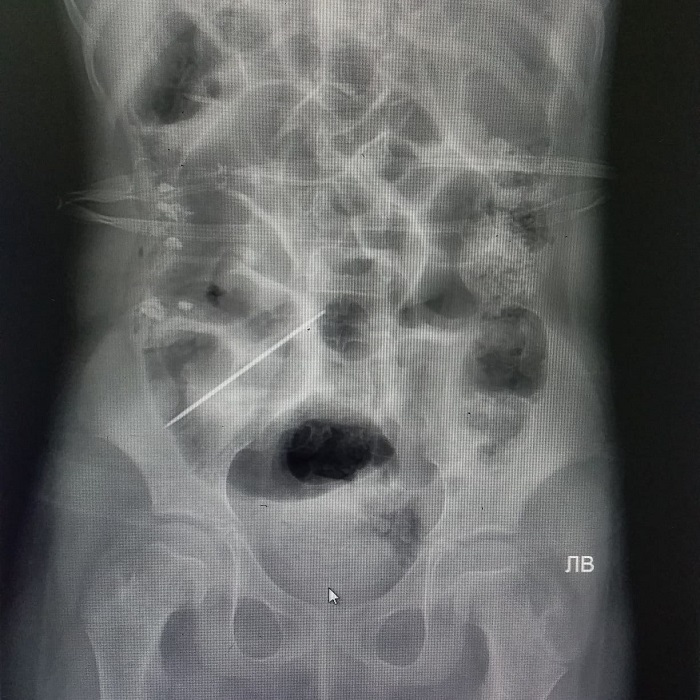

Со слов хирурга, 14 января 2020 года в детскую больницу с жалобами на боли в животе поступил подросток 2006 года рождения. При проведении рентгена в кишечнике ребенка было обнаружено инородное тело.

- На следующий день, 15 января, после подготовки подростку была проведена операция. В ходе операции из кишечника девочки извлечены клок волос и игла. На сегодняшний день состояние ребенка стабильное, - рассказал Насукан Отаргазиев.